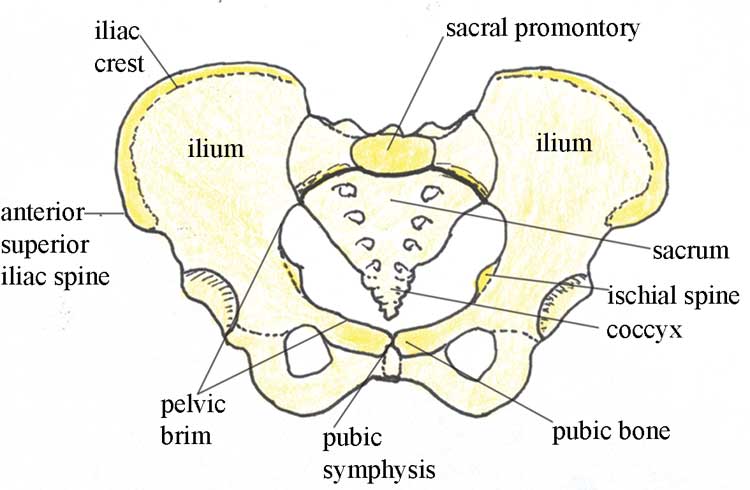

The female sacrum is shorter and wider than a males. As babies we are born with 300 bones but as we age some of those bones fuse together.

Female skulls and head bones differ in size and shape from the male skull. The female skeletal system is the most accurate and detailed 3d virtual skeleton available anywhere. The sacrum is connected to the tailbone or coccyx which is made of several fused vertebral bones at the base of the spine.

Then comes the wrist bone called the carpus the paw bone which joins the wrist and the toes known as metacarpus and then the toe bone known as the phalange. It is made up of five fused vertebral bones. The female pelvic bones are typically larger and broader than a males.

Women tend to have lighter skeleton frames than men. Together they form the part of the pelvis called the pelvic girdle. Bones are not however dead they are living tissue.